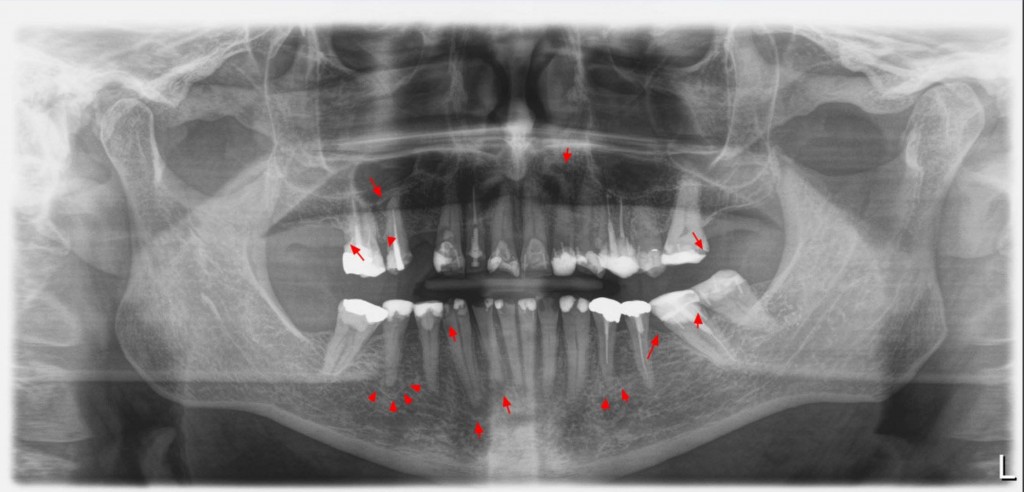

Röntgennäkymä ennen ja nyt kolme vuotta toimenpiteestä

kolme ptg

Kyseinen tapaus tuli toiselta hammaslääkäriltä jossa oltiin keskimäärin vuosittain paikattu 10 lohkeamaa ja purenta oli mennyt kokoajan huonompaan suuntaan. Kliinisessä ja radiologisessa tarkastelussa havaittiin useita reikiä, kolme tulehdusta juuren kärjessä ja lähes jokaisessa paikatussa hampaassa huonoja saumoja ja osittain irti olevia paikkoja.

Röntgenkuvissa havaitaan runsaasti paikattu, saumavuotoja, kairesta, lohkeamia

Röntgenkuvien näkymä ennen  ja jälkeen hoidon:

25311245_10155395985874091_8129600685629615683_o